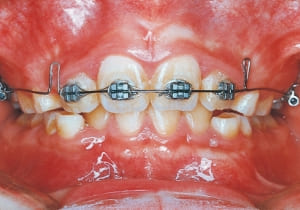

The Class II condition is pronounced, with a significant overjet of 12.5 mm(3). Although the teeth size are large, crowding is relatively mild. The maxillofacial structure has good depth and a robust bone framework(5). The mandible itself is solid , robust gonial angle, but there is significant anterior-posterior displacement relative to the maxilla(ANB 10.0°). While there is no confirmed history of thumb-sucking or similar habits, the lower lip is already pushing up against the maxillary incisors. The cause of this condition is unknown.

The first phase of treatment involved extracting the left and right maxillary deciduous canines. The space created was used to forcibly retract the four anterior teeth, thereby aiming to improve lip closure function (6–9, 11). Morphological changes suggest that lip function differed before and after treatment (6, 9). Subsequently, the first premolars erupted, but extraction is planned to secure space for canine eruption (10). A Class II molar relationship remains, but the significant overjet has improved (11).

In the maxilla, insufficient space for canine eruption was inevitable, necessitating extraction as part of the treatment plan. The maxillary first premolars on both sides were extracted during routine observation to create space for canine eruption (14). Eventually, the canines erupted and settled into relatively favorable positions (15,19,20). In the mandibular dentition, crowding was also present, leading to extraction of the mandibular first premolars on both sides. Treatment with full bracket was then initiated (17).